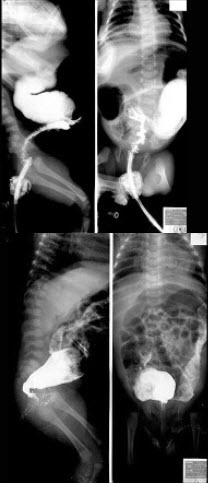

267、单项选择题

女婴,出现持续性呕吐,腹胀,如图所示,最可能的诊断为()

A.肠梗阻

B.肠扭转

C.肠闭锁

D.肠旋转不良

E.肠穿孔